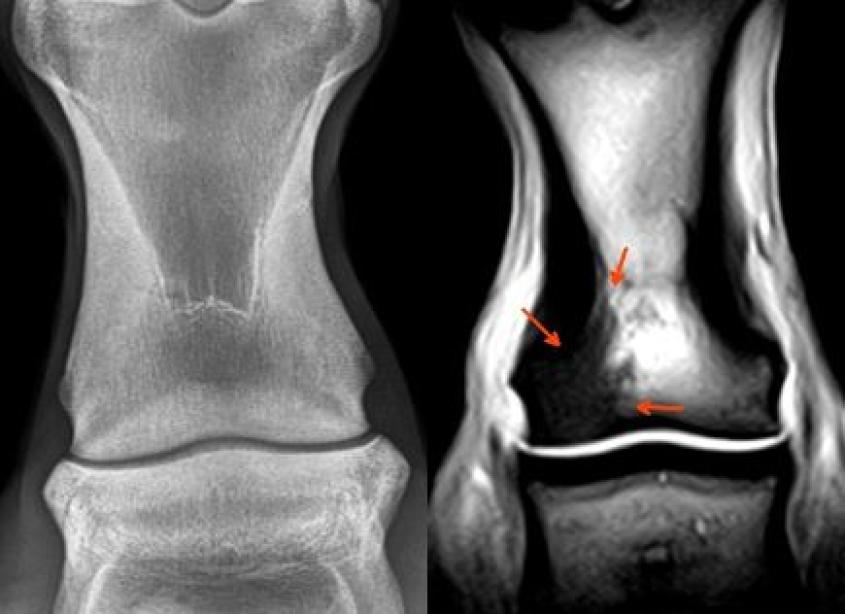

MRI images left to right: coffin joint collateral ligament injury, deep digital flexor tendon injury in foot, navicular bone flexor cortex erosion with adjacent deep digital flexor tendon damage, bone trauma in fetlock joint